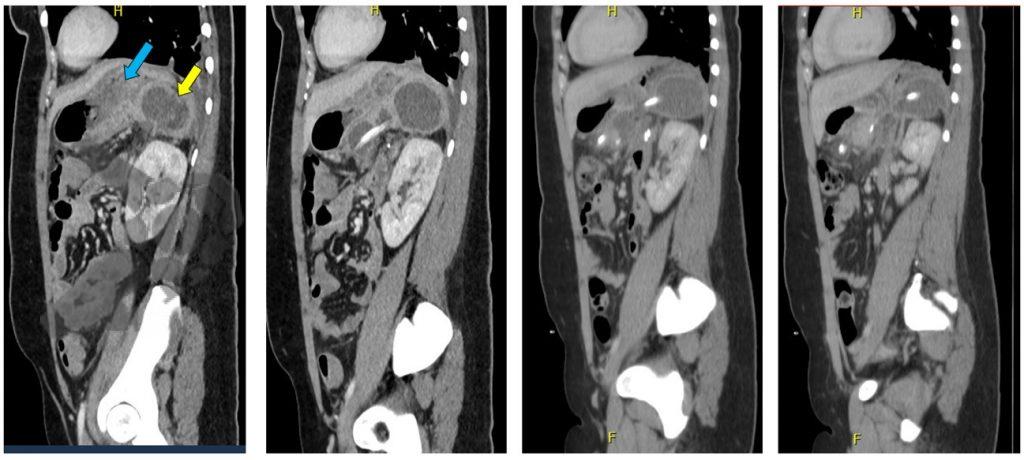

- TC de abdomen revela colección retrogástrica en contacto con el margen de resección del páncreas (Figuras 1 y 2).